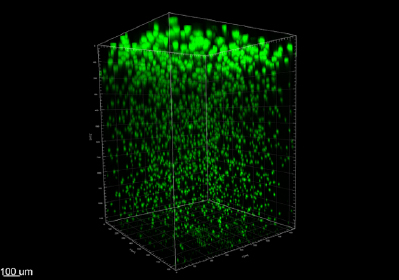

P. aeruginosa biofilm aggregates grown in an agar block biofilm assay. Bacteria (green) were stained with HCR nucleic acid probes and imaged by confocal microscopy after 16 hours growth. Biofilms promote bacterial tolerance to antibiotic treatment and play an important role during chronic CF infections. Biofilm aggregates growing near oxygen are larger at the top of the agar block than aggregates growing with less oxygen near the bottom of the agar block.

P. aeruginosa biofilm aggregates grown in an agar block biofilm assay. Bacteria (green) were stained with HCR nucleic acid probes and imaged by confocal microscopy after 16 hours growth. Aggregate surfaces were reconstructed from HCR nucleic acid staining.